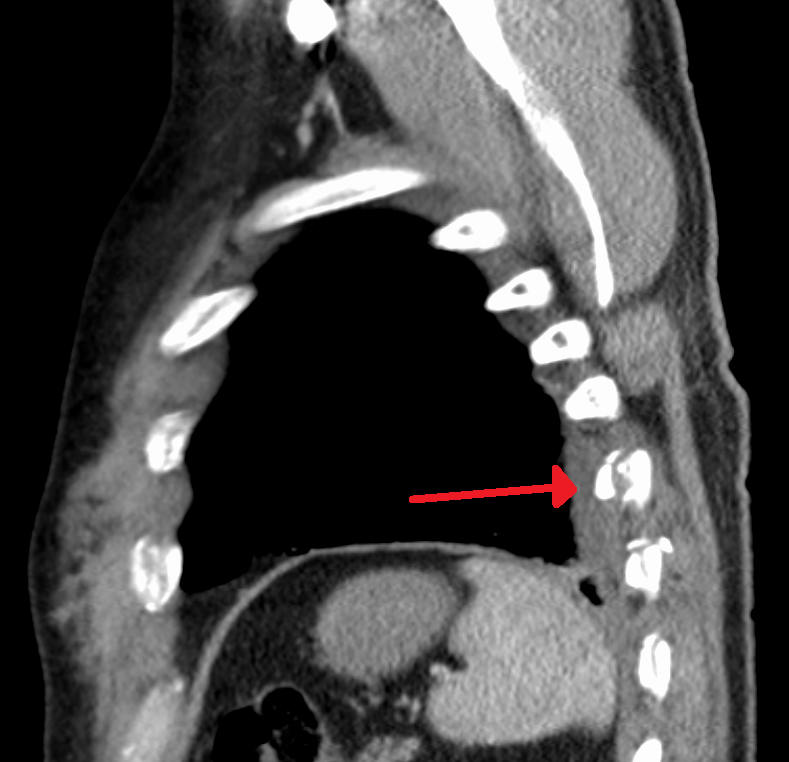

늑골 골절은 늑골에 금이 가거나 부러진 상태를 의미한다. 레크리에이션 활동 중 외상, 심폐 소생술, 질병, 심한 기침, 낙상, 자동차 사고 등이 원인이 될 수 있다. 진단은 X-선 촬영이나 CT 스캔을 통해 이루어지며, 흡입 시 통증, 흉부 부어오름, 멍, 호흡 곤란, 객혈 등의 증상이 나타날 수 있다. 치료는 통증 완화와 이차적인 흉부 감염 예방에 초점을 맞추며, 신경 차단술, 내부 고정/수복술 등의 방법이 사용될 수 있다. 합병증으로는 동요 가슴, 무기폐, 피하 기종, 혈흉 등이 발생할 수 있다.

늑골 골절은 일반적인 X-선 촬영으로는 변위 골절만 감지되고, 비변위 골절은 놓치는 경우가 많다.[13] CT 스캔은 일반적으로 두 종류의 골절을 모두 감지할 수 있다.[13]

3. 진단

기침, 재채기 시의 자발통, 골절 부위의 국소적인 압통, 흉곽 압박에 의한 간접통 등이 증상으로 나타난다. 전위가 심한 경우에는 골절편을 촉진으로 확인할 수 있으며, 삐걱거리는 소리를 들을 수 있다. X선 사진에서는 골절선을 확인할 수 없는 경우가 적지 않다.